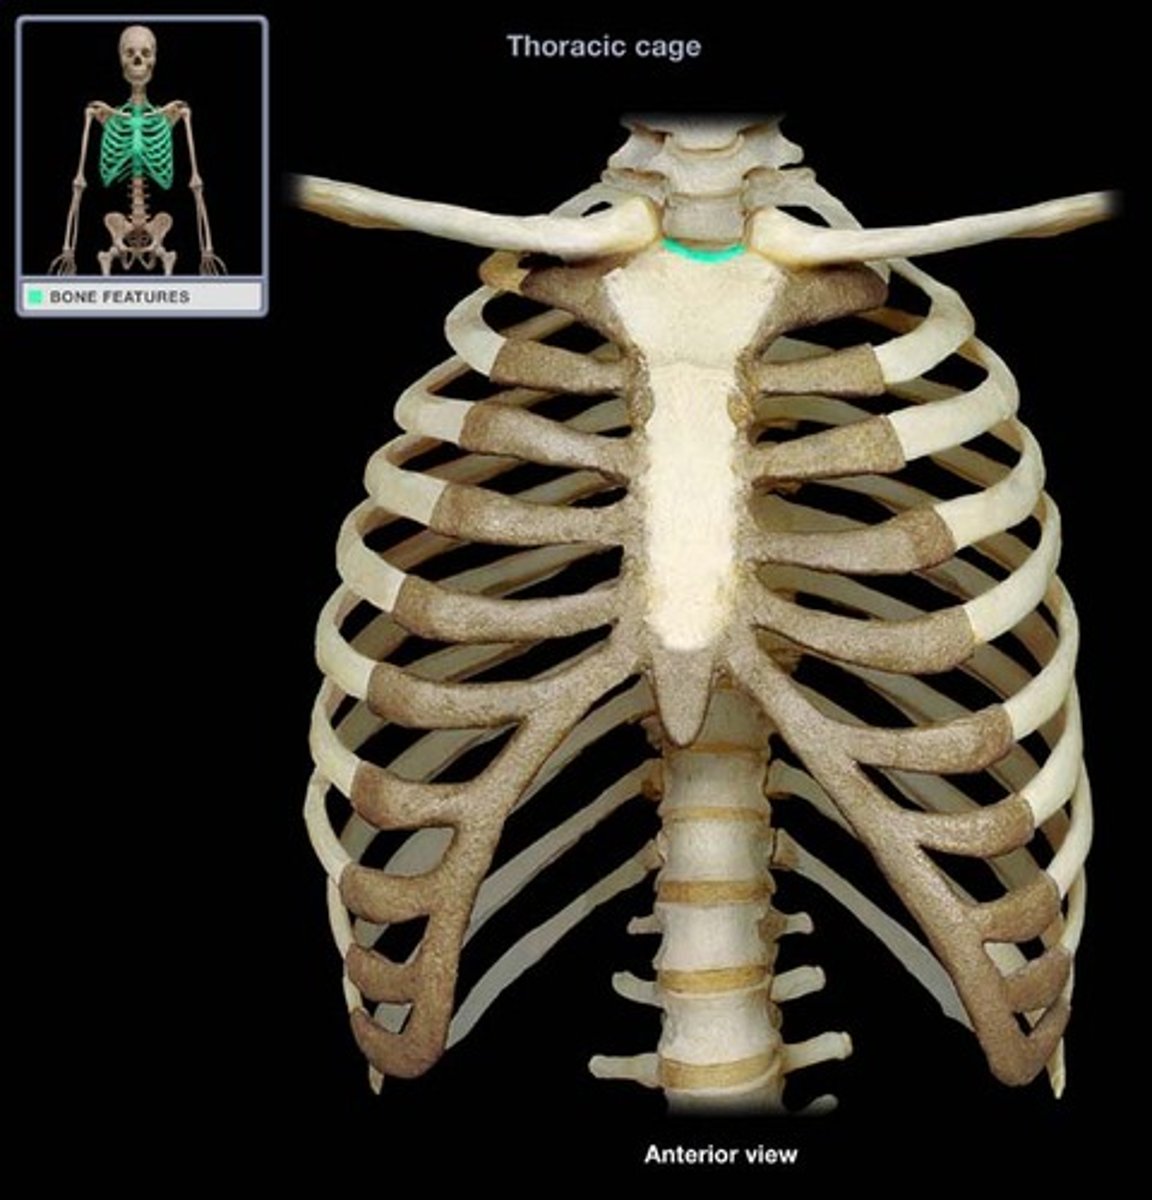

What makes up the thoracic cage?

sternum, ribs, and thoracic vertebrae

What is the function of the thoracic cage?

Protects heart, lungs, trachea, esophagus, and other thoracic organs, support upper limbs and provide muscle attachments

manubrium of sternum

Articulates with ribs 1, 2, & clavicles. Sternocleidomastoid muscles also attach here.

suprasternal (jugular) notch

superior surface of manubrium; u shaped notch

clavicular notch of sternum

Site where manubrium articulates with the clavicles

costal notches of sternum

indentations on sternum where costal cartilages from the ribs articulate

sternal angle

Ridge between manubrium and body at second rib

thoracic cage

ribs, sternum, thoracic vertebrae, encloses organs and moves for ventilation